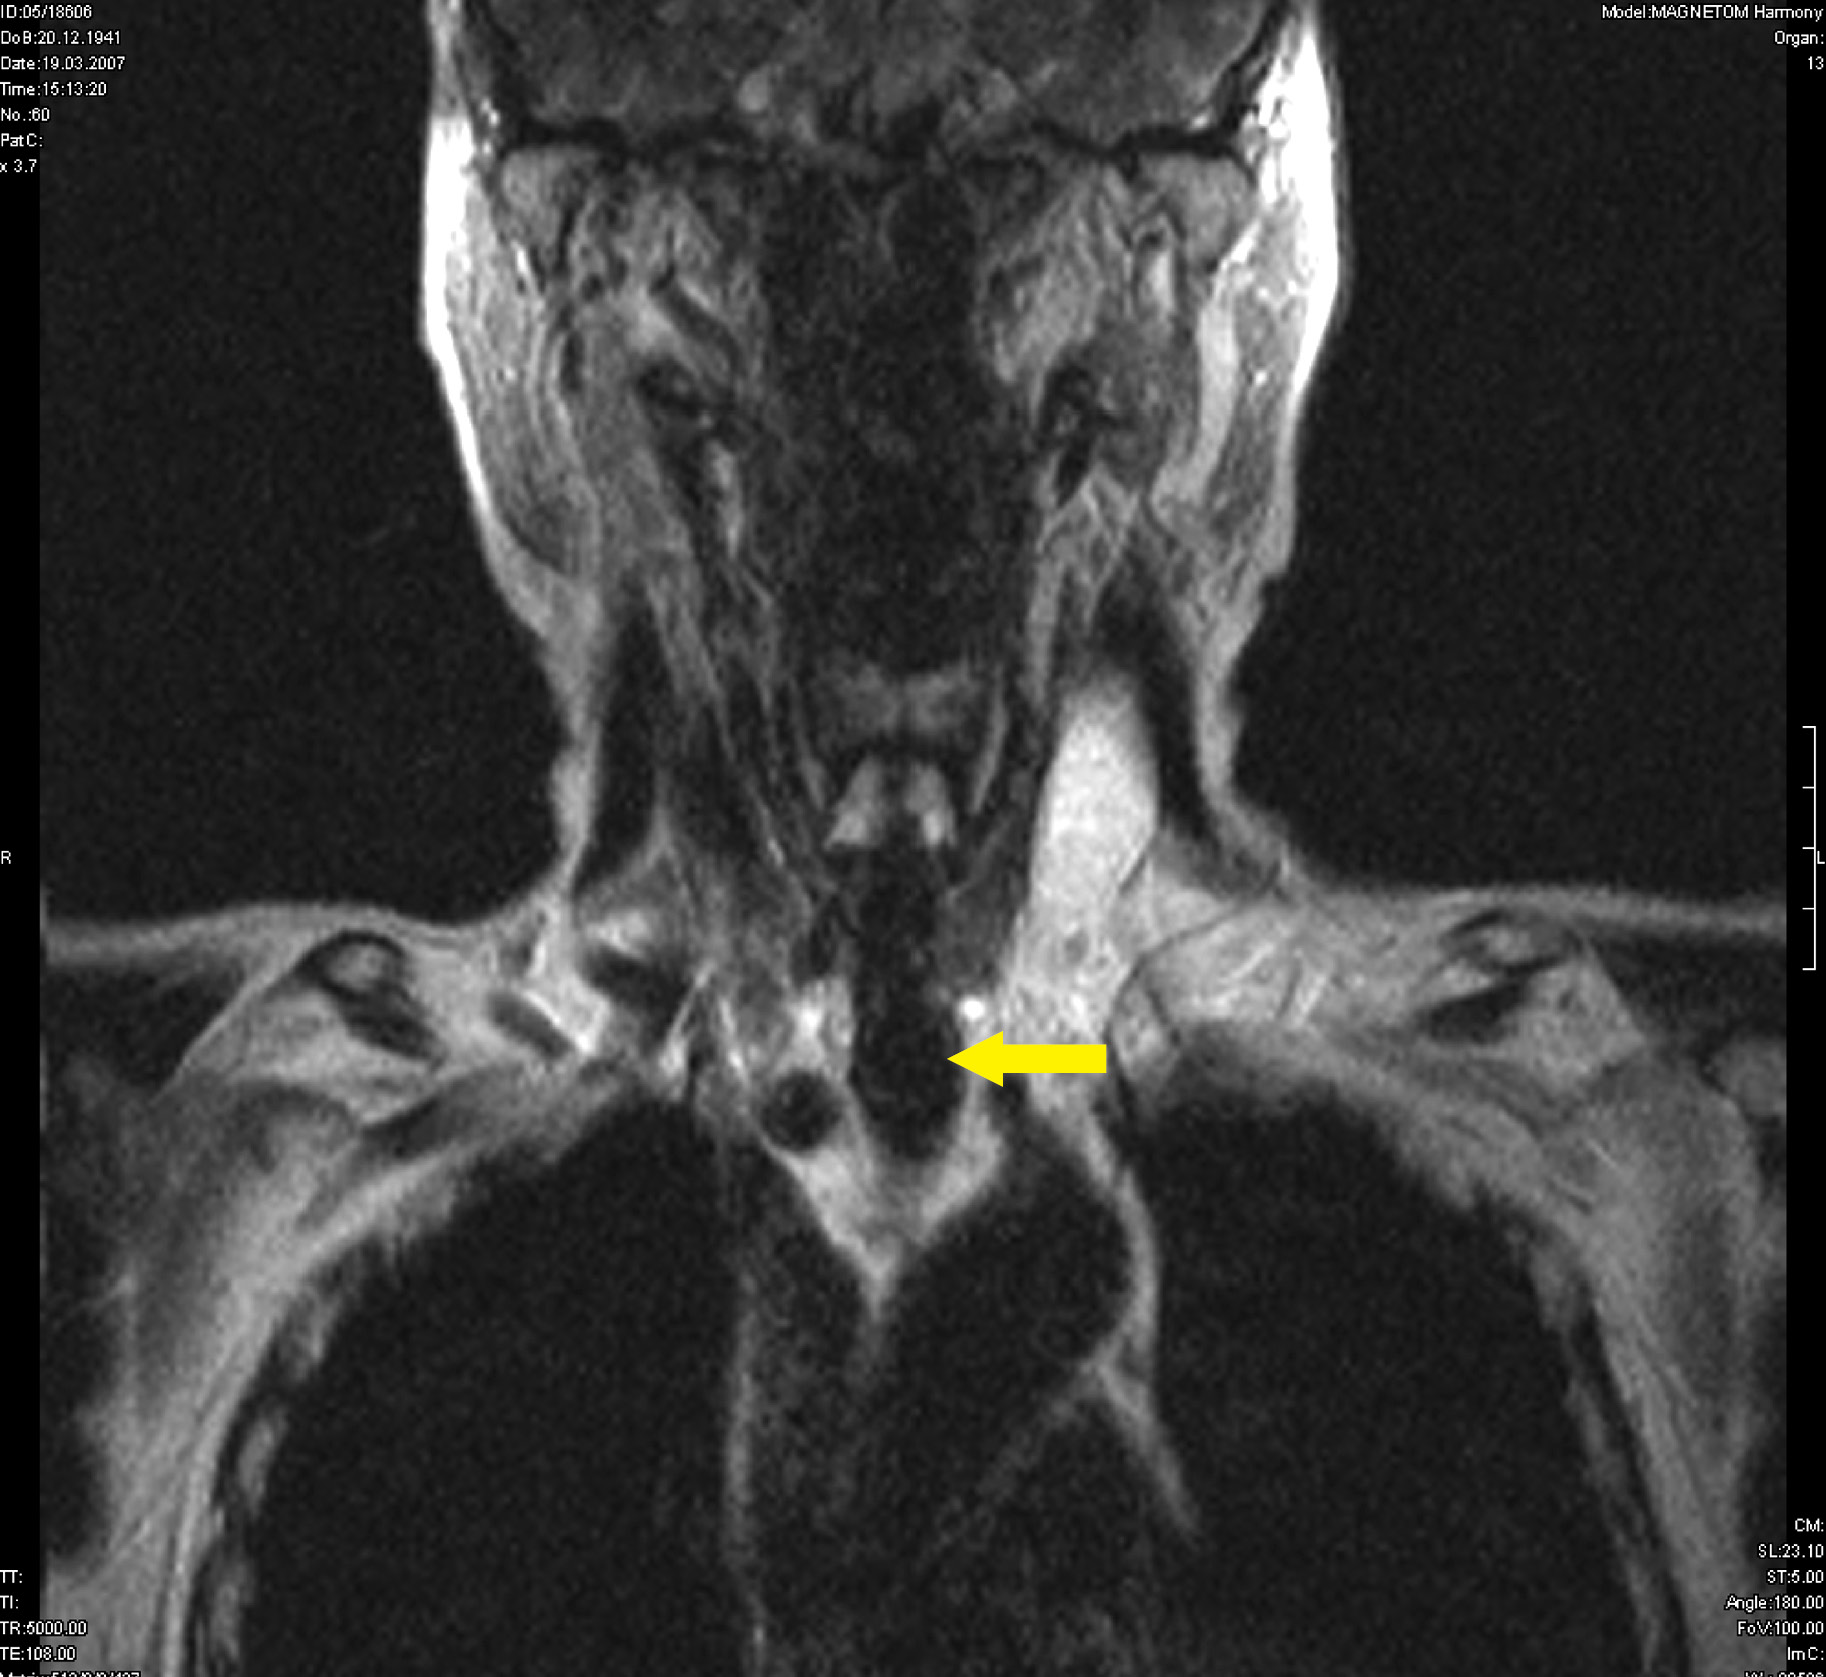

4. Рисунок 4. Больная Ш. Компьютерная томография опухоли щитовидной железы с врастанием в трахею. | |